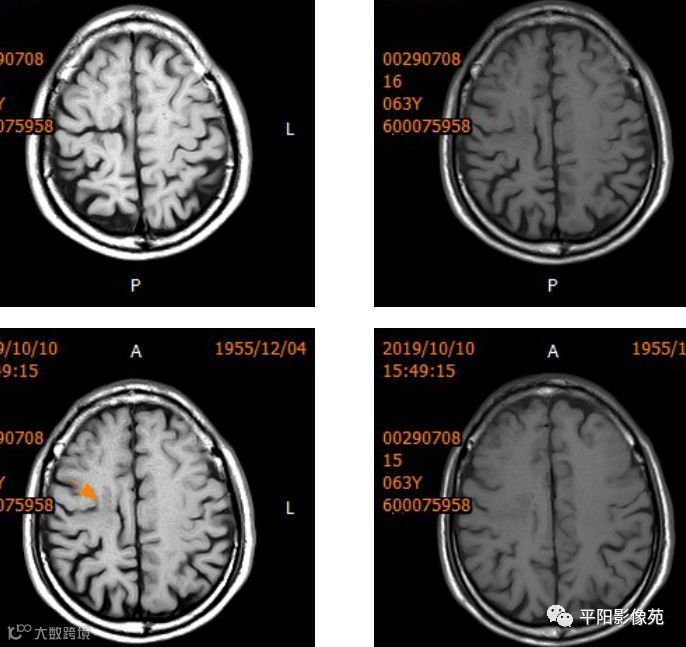

右侧额叶中央前回局部脑裂增宽,并向内延伸,周围衬以等灰质信号,呈稍长T1稍长T2信号,病灶自软脑膜向内延伸,与室管膜相连。